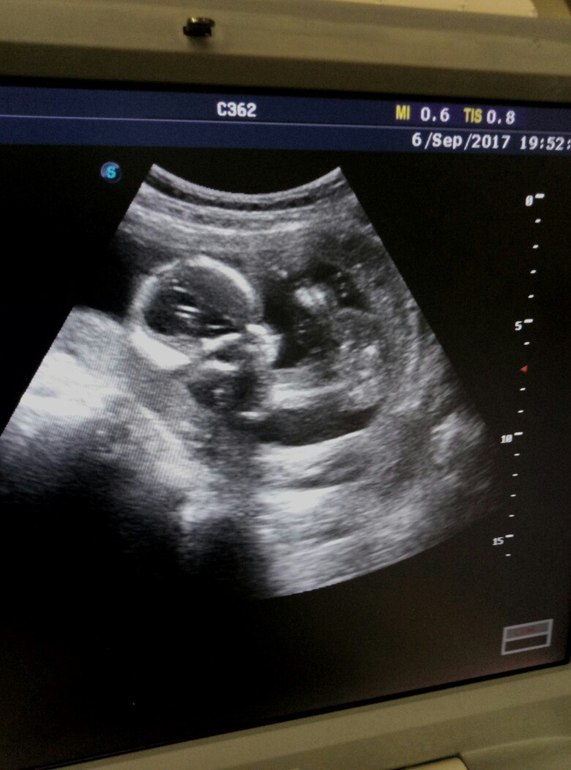

Неделю назад прошла плановое УЗИ, если это можно так назвать 😀 Все УЗИ длилось минут 15, из них большая часть времени ушла на оформление выписки. Сама процедура минут 5 от силы. Все молча... Я смотрела в потолок, мысленно разговаривала с малышкой и молилась, чтобы все хорошо было. Наконец, врач сказала: "Все хорошо" и развернула ко мне монитор.

Ну, как обычно, слезы на глазах 😍 Пузырик плавала, потом почесала конкретно лоб, открывала и закрывала ротик, потом врач сказала: "Смотрите! Она смотрит прямо на вас!". И правда, голову развернула к камере))). Сидела на попе в этот раз.

Фото мне и не подумала распечать, выключила все и пошла выписку печатать. Я говорю - А фотографию?

Она - А что, надо? Что ж вы раньше не сказали??

Ну как же не надо... Она нехотя снова включила монитор, снова намазала живот... Фотографию я сделала с экрана на телефон....